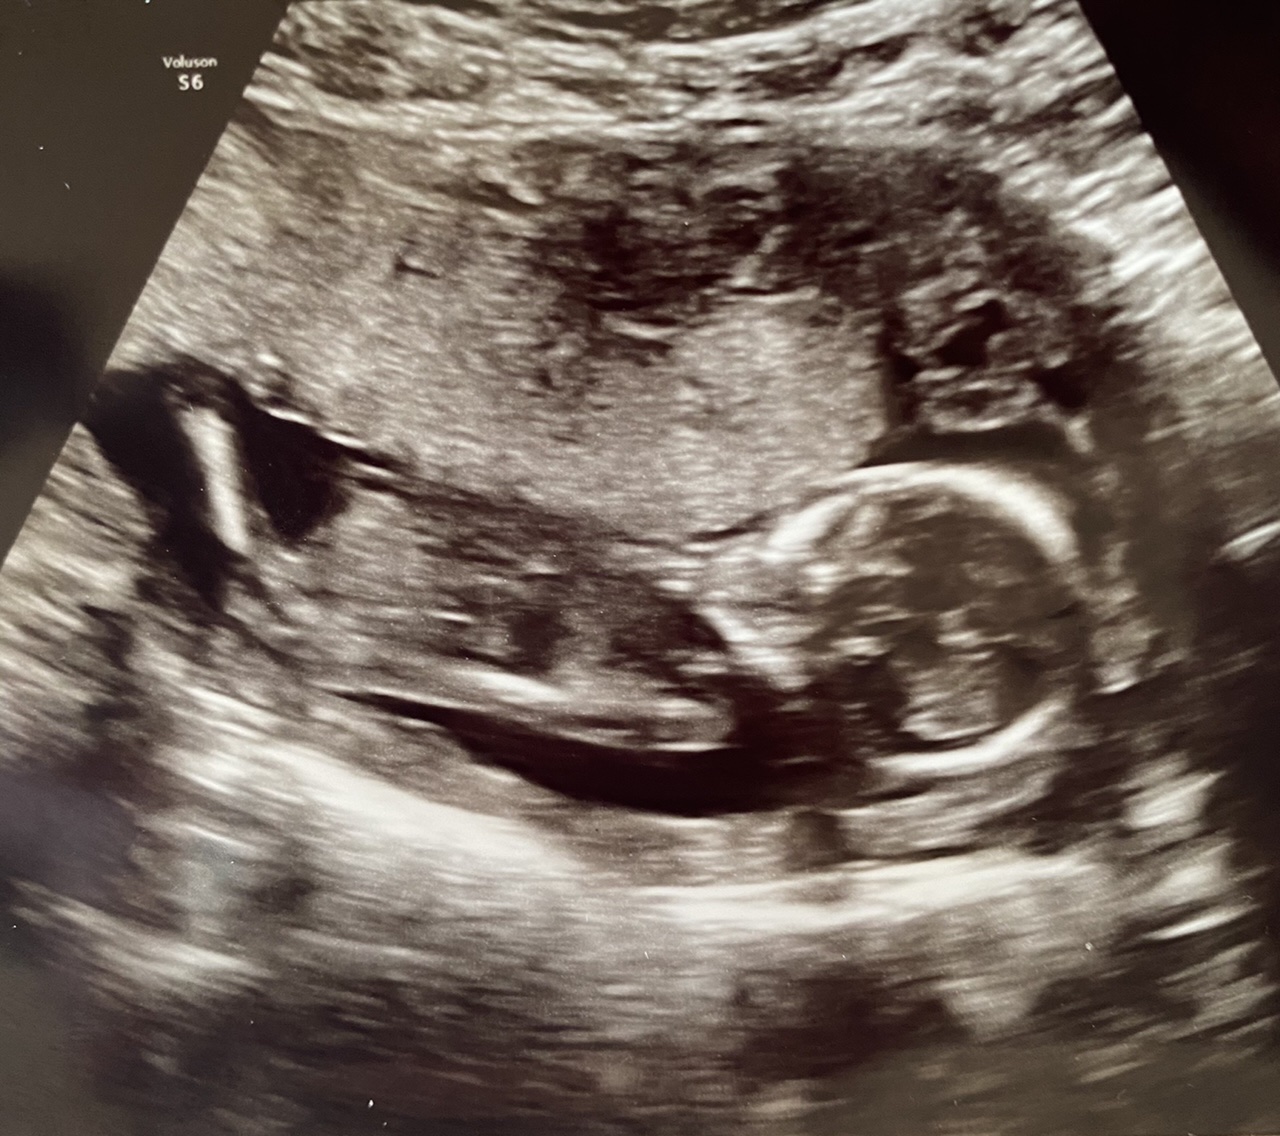

Any nub or skull guesses? The scan was done at 12 weeks 4 days.

Ok, top pic, you can clearly see the leg, right?? There's a sticky uppy thing where the leg meets the torso, and then a little something underneath? That looks like it may be penis and testicles to me.

No, the tech has the ability to zoom on to show the halfshot of the baby. So the outer leg isn't visible in this.